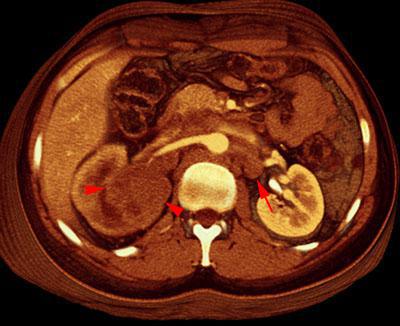

Carcinoma medular renal

VR seccional. Visión axial caudal. Lesión tumoral de valva posterior del riñón derecho (puntas de flecha). Disminución de la contrastacion de la cortical renal indicando infiltración vascular. Adenopatías paraaórticas izquierdas (flecha)